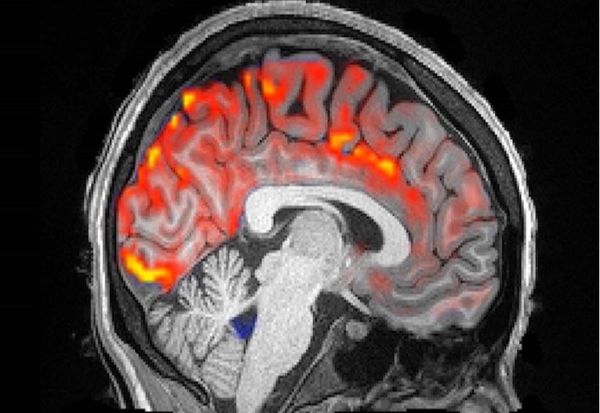

Нашето тело буквално „го пере“ мозокот секоја вечер, а невронаучниците сега направија фасцинантна видеоснимка што го покажува овој ноќен процес на пулсирање во акција.

Според најновите истражувања, во текот на ноќта низ нашиот мозок течат бранови на цереброспинална течност, ритмички пулсирајќи додека спиеме, истовремено отстранувајќи ги штетните токсини. Цереброспиналната течност го исполнува просторот околу мозокот и 'рбетниот мозок и ги штити од директен контакт со коскениот ѕид околу мозокот.

Во комбинација со мозочната активност на бавен бран и намалувањето на протокот на крв што се случува додека спиеме, овие бранови на цереброспиналната течност изгледаат како да ги „мијат“ непотребните протеини и другите излишни остатоци.